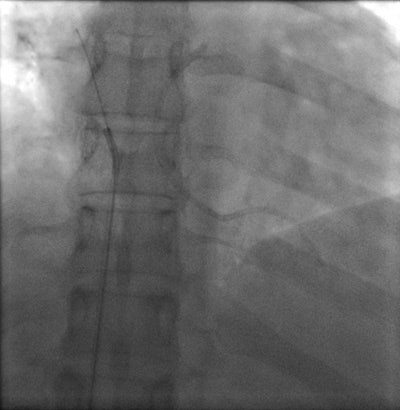

Chest radiograph of a 32-year-old woman shows cardiac migration of the proximal fragment of a fractured portacath. All images courtesy of Drs. Jamal Al Deen Alkoteesh and Maysam T. Abu Sa'a.The portacath fracture was incidentally discovered on chest radiograph, which showed cardiac migration of the proximal fragment. Echocardiography was performed and showed preserved left ventricular function with ejection fraction of about 50% to 55%. No regional wall motion abnormalities seen. Linear shadow was seen on echocardiography, representing the retained fragment.

Percutaneous retrieval of the retained fragment of the fractured portacath catheter was successfully accomplished on the second attempt. Following prepping of the right groin, the right femoral vein was punctured and an 8 French sheath was inserted. Selective catheterization of the right ventricle was performed using a 6 French catheter. A 25-mm snare was used to capture the migrated retained fragment. It was then removed successfully without immediate complications.

The postoperative radiograph showed no residual fragments.

Postoperative chest radiograph.Discussion